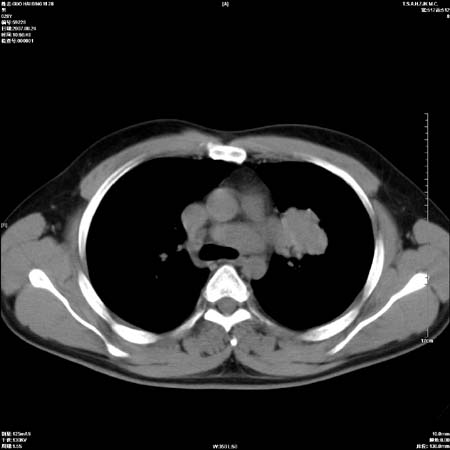

男性,28岁,体检发现左肺病变,患者只有背部隐痛感,哀哉,真不忍心下诊断啊。

左肺门区软组织肿块,左肺上叶支气管开口消失,纵隔内见肿大淋巴结,考虑左中心型肺部,可以做纤支镜取病理确认.

左肺肺门区肿块影,分叶明显:诊断肺癌应该没有疑问。

左肺肺门区肿块影,分叶明显,左肺上叶支气管开口受压,纵隔内见肿大淋巴结,考虑左中心型肺癌。

左侧肺门区见一块状病灶可见分叶,纵隔内及左肺门见肿大淋巴结,应该是周围型肺癌而不是中心型肺癌,原因有以下2点,1未见阻塞肺气肿和阻塞性炎症,这么大肿块如果是中心型肺癌就是未分化型或小细胞型肺癌不出现阻塞性肺不张也应该有阻塞炎症或阻塞性肺气肿,2如果是中心型肺癌临床出现最早的症状是咳嗽(此时可无任何异常影象),而此人这么大肿块只有背部隐痛是体检才发现无法解释.

左肺门区分叶状软组织肿块,纵隔内有肿大淋巴结,诊断肺癌应该问题不大。

直接下肺癌诊断还太早,病灶较大,估计5cm以上,但阻塞性改变及对临近纵隔及支气管侵犯不明显,密度较均匀,弓旁见一单个淋巴结,需要排除炎症性肿块及腺瘤,平滑肌瘤等。